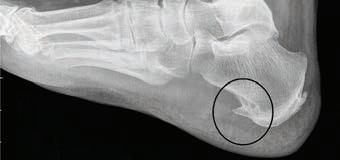

Сохраним здоровые и красивые ноги надолго! 32 Самые распространенные болезни стоп

Пяточная шпора

Фасциит: эффективные методы лечения заболевания

Здоровье ваших ног?

Плоскостопие – одна из наиболее известных патологий стопы. При этой болезни происходит снижение высоты сводов – естественных изгибов подошвы. Уменьшение сводов ведет к снижению амортизации и перегрузке всех суставов. Плоскостопие может врожденным и приобретенным, поперечным, продольным или комбинированным.

СИМПТОМЫ ПЛОСКОСТОПИЯ

К основным симптомам развивающегося плоскостопия можно отнести:

• усталость и тяжесть в голенях после ходьбы,

• судороги икроножных мышц,

• ноющие боли в пояснице,

• тяжесть и дискомфорт в коленных

суставах,

• увеличение размера стопы,

• боль в голеностопе,

• наличие мозолей и натоптышей

и прочее.

В медицине есть закономерность: сначала болит не причина проблемы, а страдающие от нее отделы. Поэтому сама плоская стопа часто совершенно безболезненна. Боли, связанные с этой проблемой, обычно проявляются в коленях, тазу, пояснице и шее. Лишь на последних стадиях плоскостопия неприятные ощущения доминируют именно в проекции суставов стопы.

ЧТО ДЕЛАТЬ ДЛЯ ИЗБАВЛЕНИЯ ОТ БОЛИ?

Форма ног во взрослом возрасте практически не меняется. В определенной степени на развитие стопы можно повлиять где-то до 6-8 лет. Но даже с аб-

солютно плоскими стопами можно провести коррекцию и защитить опорно-двигательный аппарат от осложнений.

Наиболее эффективно улучшают амортизацию стоп и защищают колени ортопедические стельки. Выступы супинаторов не только поддерживают правильную форму сводов, но и стимулируют мышцы-стабилизаторы. В зависимости от формы и материала стельки могут больше амортизировать, массировать, разгружать или стимулировать стопы.

• Ортопедические стельки для повседневной обуви. Оснащены каркасом, который стимулирует мышцы и корректирует своды.

• Спортивные модели. В таких изделиях акцент сделан на максимальную амортизацию. Они подходят для бега, игровых видов спорта, катания на лыжах и прочего.

• Стельки для обуви на высоком каблуке. Модельные стельки имеют уникальную форму для поддержки переднего отдела стопы.

• Индивидуальные ортопедические стельки. Именно в таких изделиях можно добавлять специальные элементы для изменения позиции колена, поворота стопы и голени.

Если боль присутствует долго, разбираться нужно и с самим коленом. Хорошо справляются с болью эластичные бандажи с силиконовыми вставками. Они мягко поддерживают и массируют сустав, улучшают кровоток и комфортно стимулируют стабилизирующие мышцы. p